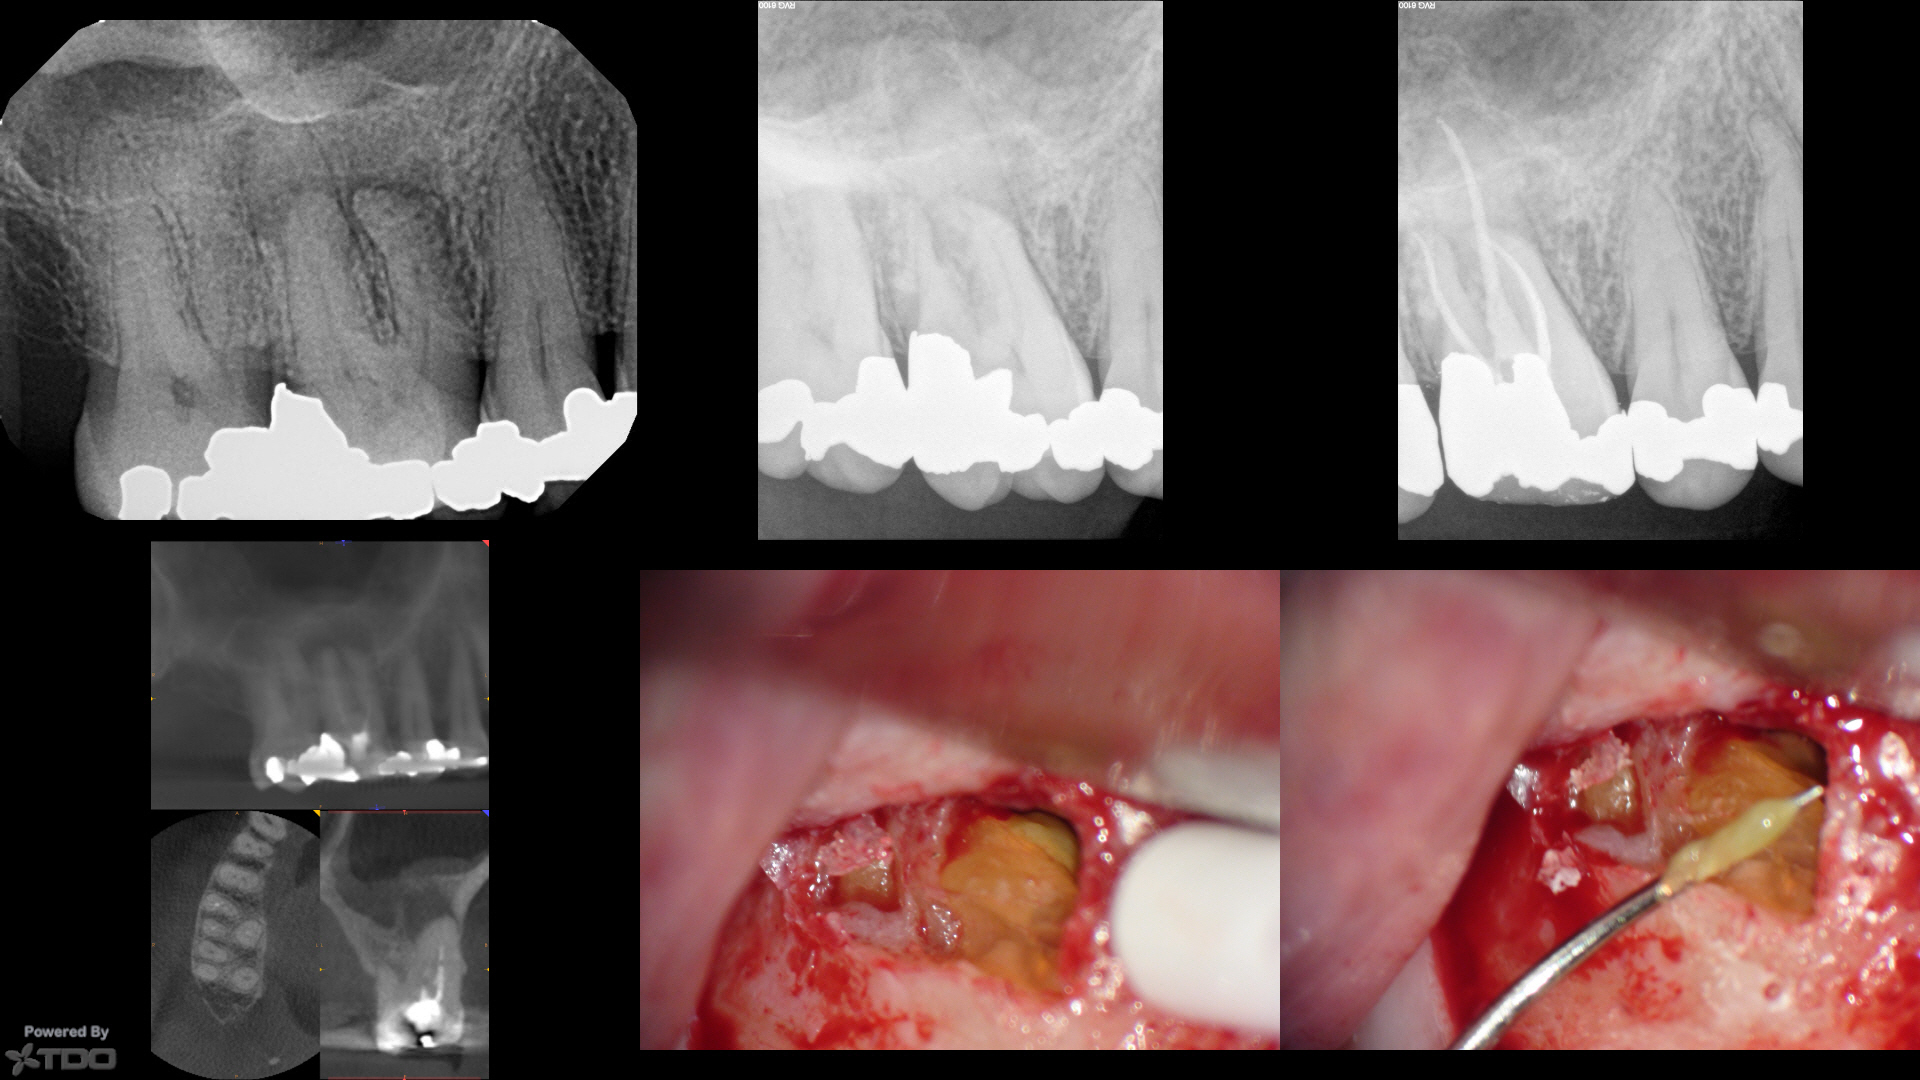

We reflected a flap to discover the green gnar. Most of these cases that are refractory that I re-enter surgically have some sort of root-end gnar. Green gnar, yellow gnar and sometimes orange gnar with sparkles.

Here, I just resected the MB/DB roots to what appeared to be clean bone, curetted out the crypt, placed a Collaplug (to help form a clot…I don't know if it matters). I did not retroprep or retrofill.

If one is very careful doing periapical surgery and sneaks up on the root end with magnification, most of these refractory cases have some sort of accretion/gnar around the root ends.